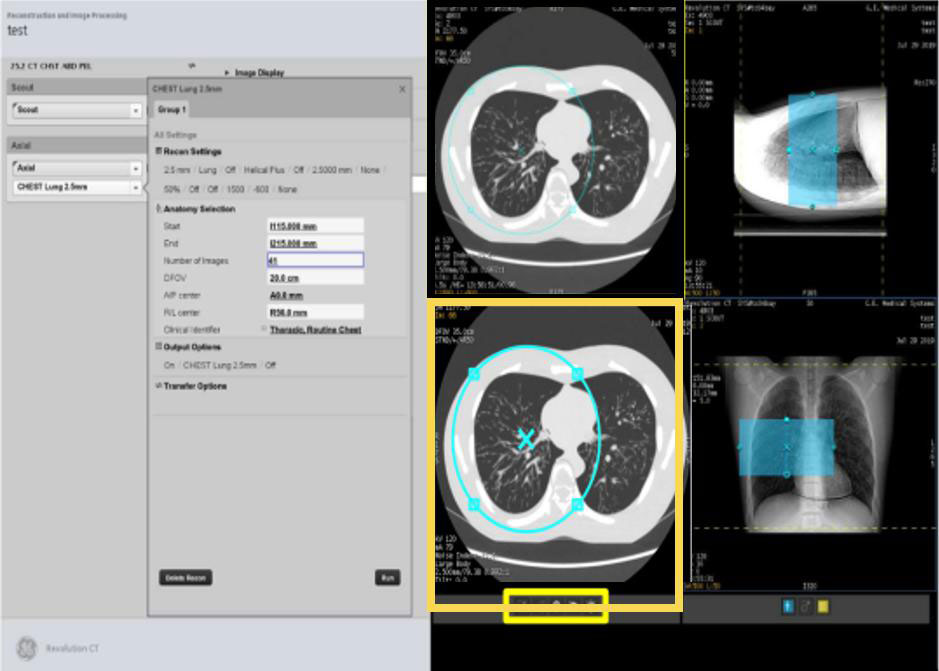

・リコン設定、レトロリコンの変化

Ascendでは左画面が撮影設定画面、右画面がリコン設定画面となっている。右画面では検査全体のリコン設定(スライス厚、関数、MARの有無など)が一目で確認できるようになっている。

従来のレトロリコンではシリーズ名、スライス厚、関数、IR強度、ww/wLの変更などをレトロリコンをする度に変更する必要があった。操作に慣れているスタッフでもいずれかの変更忘れの可能性があり、その場合はもう一度レトロリコンを行っていた。

Ascendのレトロリコンは、撮影時に使用したプロトコル画面をそのまま使用出来るようになっており、撮影プロトコルにあらかじめリコン設定を組んでおけば撮影終了後にそのリコン設定を使用することが可能である。さらにシリーズの複製機能からリコン設定を複製することや、 PACSへの自動転送機能も追加されており、従来のレトロリコンでストレスに感じていたことは解消されている。

Ascend_Satodaiichi07.jpg

Fig6. レトロリコン設定画面